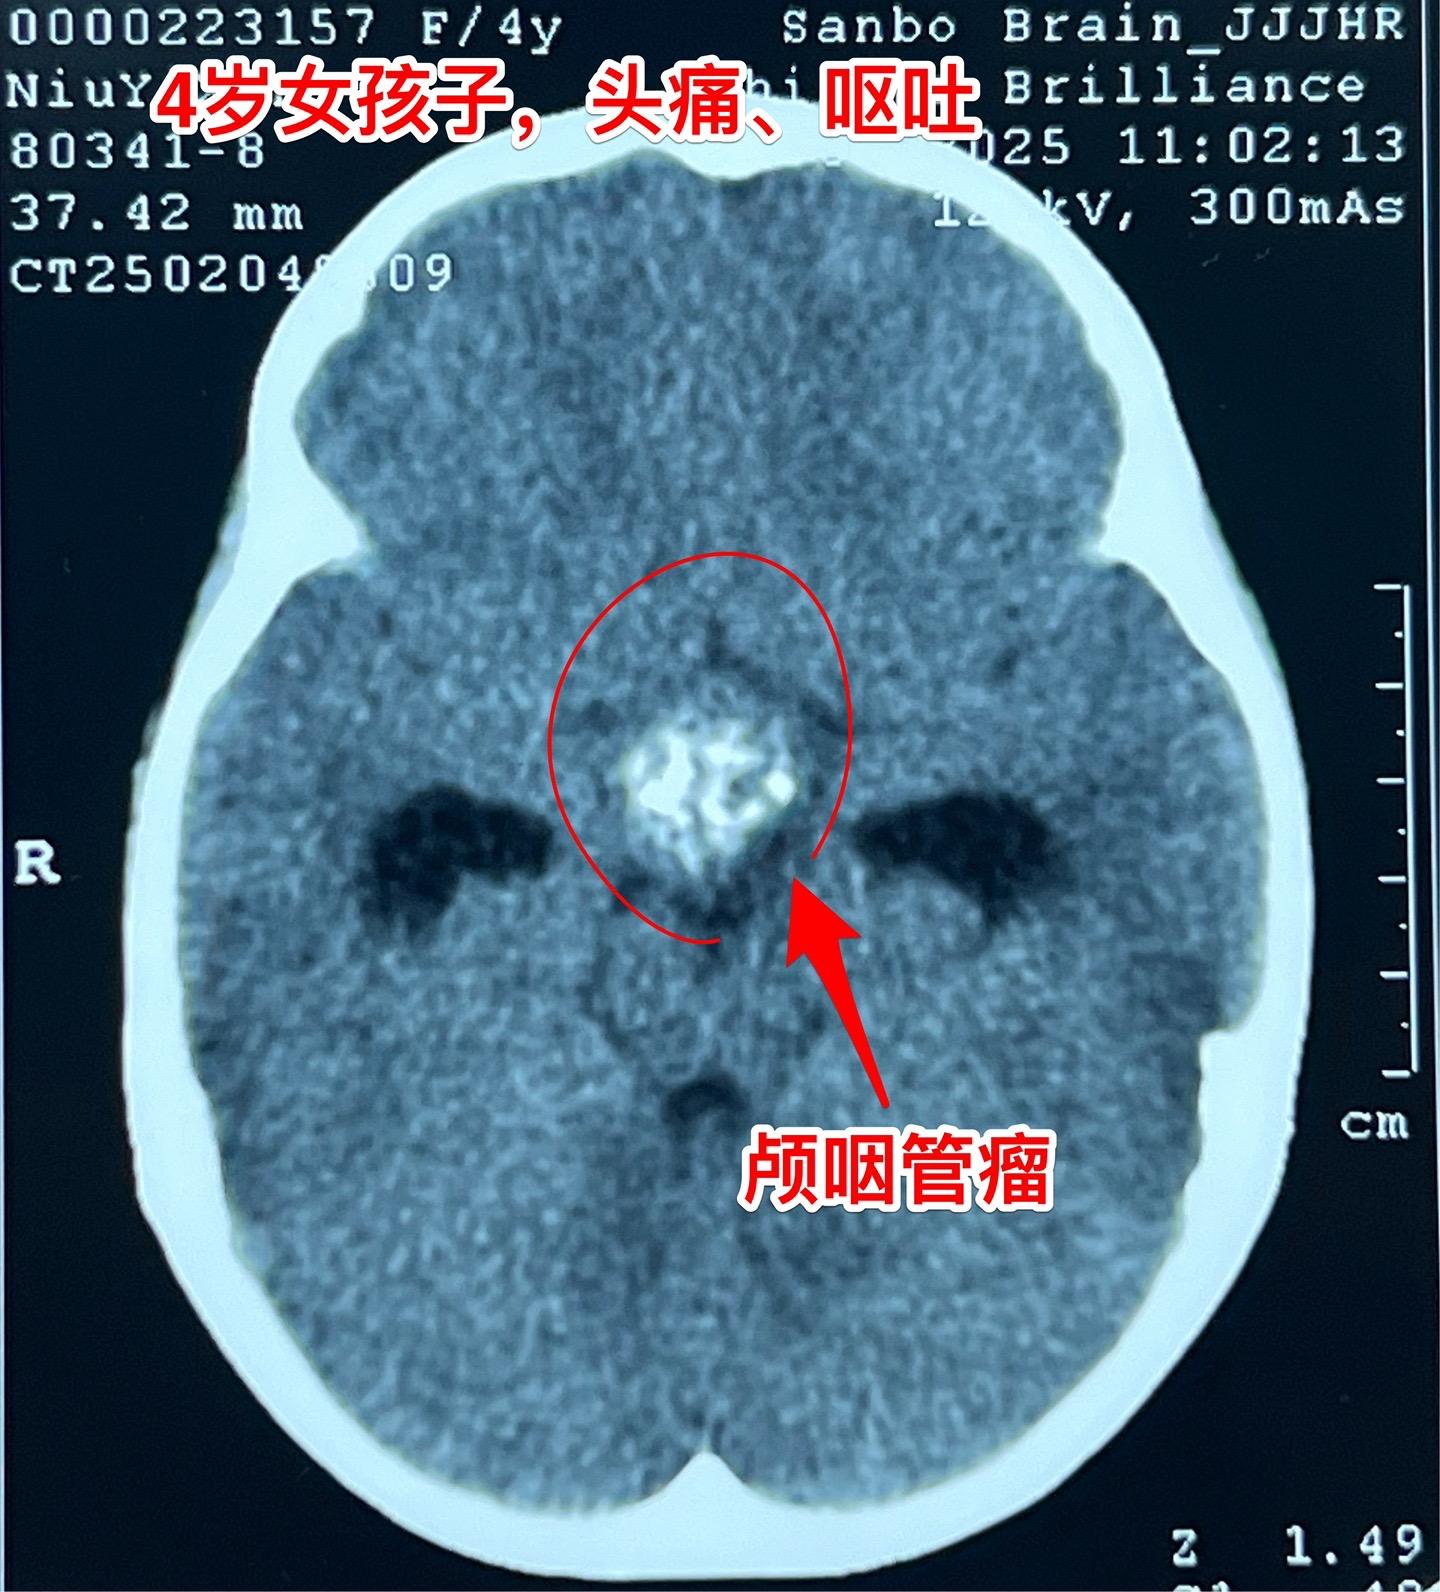

除夕当天发现颅咽管瘤,正月初七到三博住院。西安市的四岁女孩子,一个月前就开始出现头痛、间断出现呕吐,病情越来越严重,于1月28日就是除夕当天,在西安市行磁共振检查发现颅咽管瘤,伴有脑积水! 简直就是晴天霹雳! 在传统佳节里孩子的一家人处于诚惶诚恐之中。孩子头痛伴有呕吐,在当地医院每天都要输入甘露醇才能减轻症状。 正月初七一家人到三博脑科医院来住院。 正月初八正式上班,小孩子仍然有颅高压症状! 正月初九作了开颅手术,顺利切除